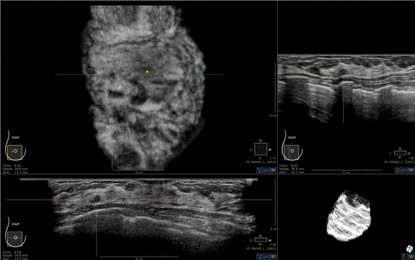

3-D volumetric ABUS

The Siemens and U-Systems stand-alone devices utilize a large-format transducer that acquires a single volume of the breast automatically in less than 60 seconds. The devices image a much larger portion of the breast as a volume, with 3-D reconstruction for a coronal plane and two standard orthogonal planes for review on a proprietary workstation.